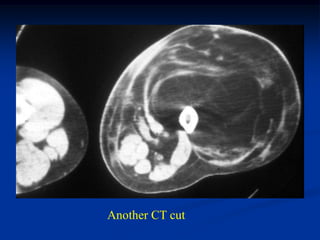

Case #295.1           Recurrent hemangioma

24 year female with recurrent hemangioma triceps

Case #295.1 Recurrent hemangioma phleboliths 24 year female with recurrent hemangioma triceps